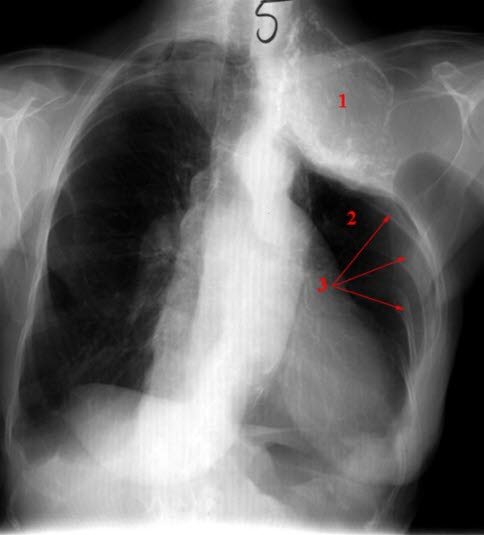

Torakoplastikk med oljeplombe

Behandlet med torakoplastikk (2). Normale costae nedenfor (3)

Oljeplombe over venstre side (1)